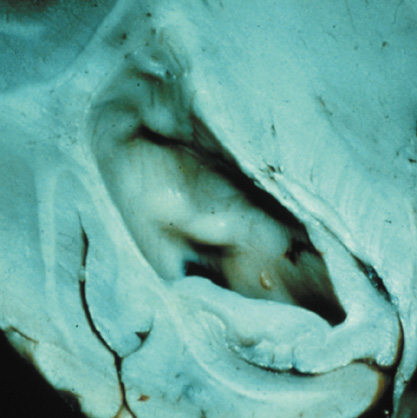

OPTIC NERVE GLIOMAS

Optic pathway gliomas arise from the astrocytes of the optic nerve. Most are pilocytic astrocytomas and typically remain intradural, extending in the subdural space. Malignant transformation is rare. There appear to be two growth patterns62:

- Perineural growth pattern, correlating with a diagnosis of NF1. The tumor expands in the subarachnoid

space and the optic nerve is compressed as a central ribbon. On

T2-weighted MRI, this may be seen as a low-intensity core with surrounding

high-intensity rim. Increased tortuosity of the optic nerve is also

associated with this growth pattern (Fig. 5).63

- Intraneural growth pattern, correlating with the absence of NF1.